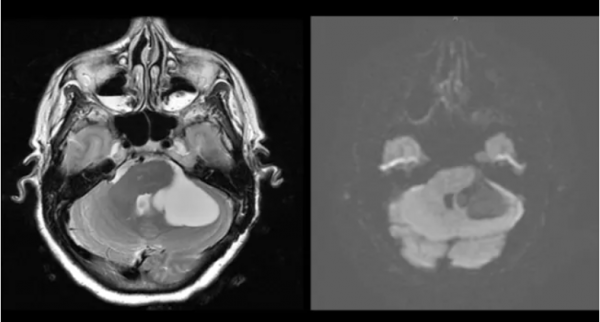

病例9

患者女,30歲,因頭痛加重、噁心、行走困難就診。MRI顯示CPA內囊性病變(左),無彌散受限(右),結果與蛛網膜囊腫一致。通常良性的蛛網膜囊腫被認為是由胚胎形成過程中異常的蛛網膜層形成引起的。然而,在極少數情況下,異常的腦脊液流動可產生蛛網膜囊腫,並導致其增大,壓迫腦幹結構。蛛網膜囊腫可發生於腦或脊柱的任何部位;最常見的部位是顱中窩(>50%),其次是顱後窩。CPA蛛網膜囊腫通常表現為共濟失調,隨後出現頭痛。